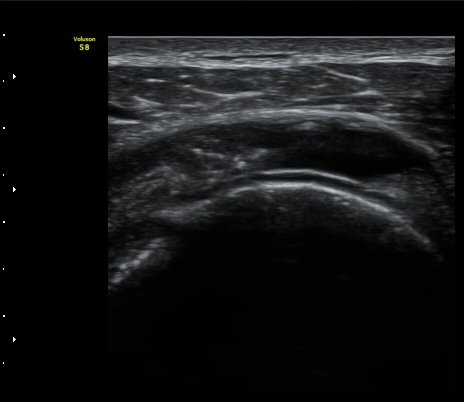

À̵ιڱ٠Ⱦ´Ü¸é°Ë»ç¿¡¼­ °üÀý³» ¼ö¾×Àú·ù´Â °üÂûµÇÁö ¾Ê´Â´Ù(»çÁø 1)